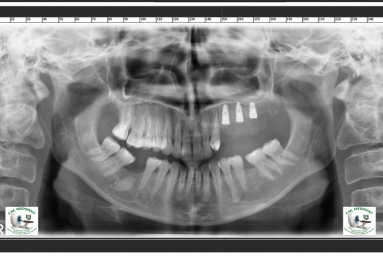

Initial situation: the patient had a an incorrect bridge for five years in the left maxillary area, this caused the extraction of the posterior tooth that was sustaining the bridge together with the wisdom tooth then three implants were inserted in the maxillary bone.

After the osseointegration of the implants three porcelain and zirconium crowns were made. At the same time full ceramic crowns were made for the left canine and the two right premolars, which had deep cavities and needed root canal treatment.